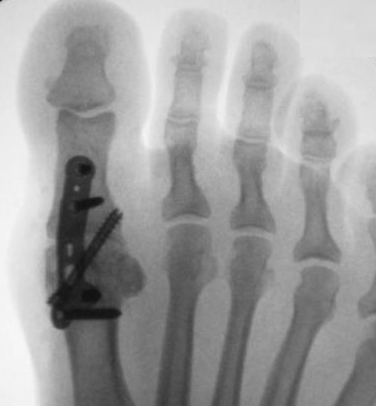

• Ressecção do dorso da cabeça do 1° metatarso

• Objetivo é uma dorsiflexão de pelo menos 70° intraoperatório

• Limita-se na ressecção de até 30% da cabeça do 1° metatarso